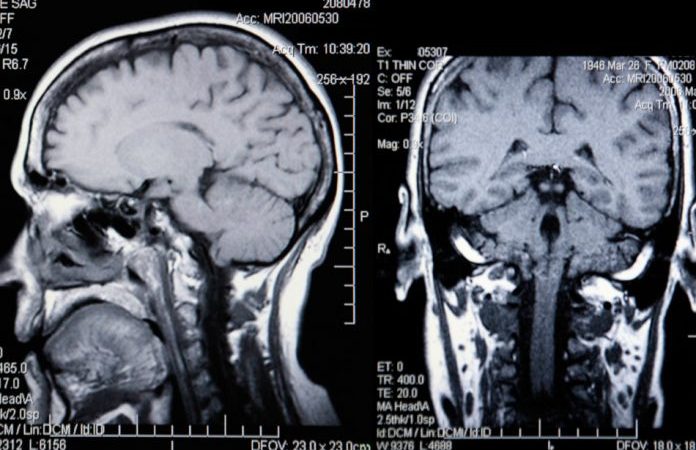

Также испытуемые прошли сканирование мозга для измерения его объёма и кровотока. С помощью анализа крови у них определили степень воспаления в организме и уровень сахара в крови.

Через два года учёные выявили, что по сравнению с контрольной группой у людей с диабетом сильнее снизилось количество серого вещества, а регуляция кровотока в головном мозге уменьшилась в среднем на 65%.